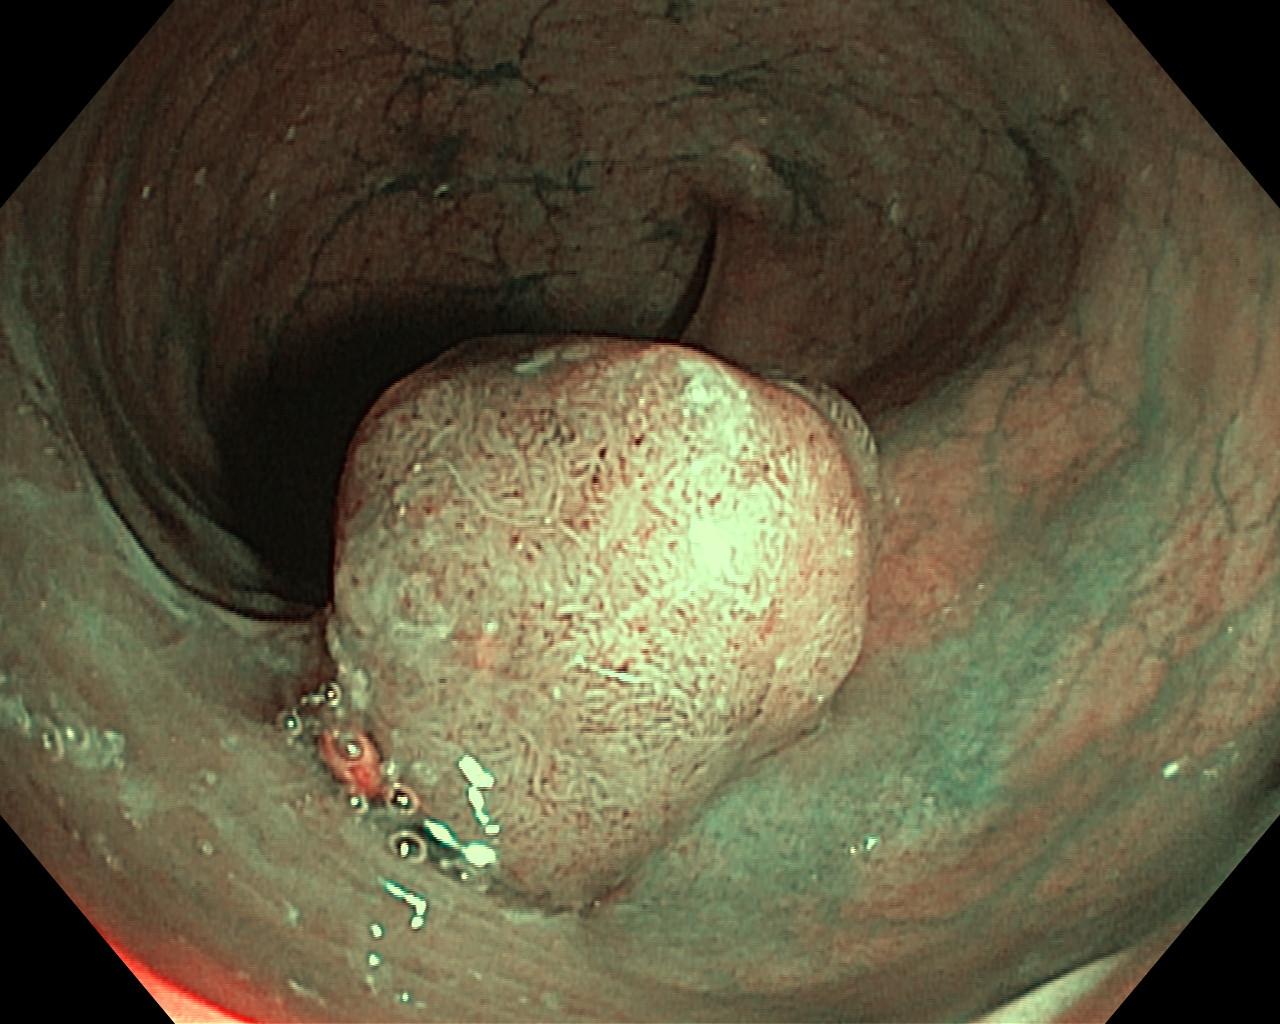

Polipy